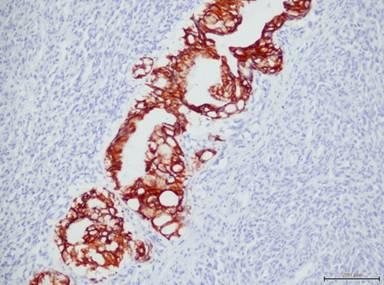

Immunohistochemistry was performed on an automated immunostainer by the avidin-biotin complex technique, using monoclonal antibodies to pan-cytokeratin, carcinoembryonic antigen, vimentin, smooth muscle actin (SMA), desmin, myogenin, CD68, CD117, S-100, CD34, p53, K-ras and Ki-67. We observed that the adenocarcinomatous component was positive for pan-cytokeratin and carcinoembryonic antigen (Figure 4). Both components were positive for p53 and K-ras, but they were negative for desmin, SMA, myogenin, CD68, CD117, S-100, and CD34. The Ki-67 proliferation index was 2%. The sarcomatous component exhibited diffuse immunoreactivity for vimentin (Figure 5) and focal immunoreactivity for SMA. Besides, two of sixteen peri-pancreatic lymph nodes showed a metastasis of the adenocarcinomatous component.

Figure 4. Carcinoembryonic antigen was positive in adenocarcinomatous component but negative in sarcomatous component (adenocarcinomatous area is in the center of the figure). |